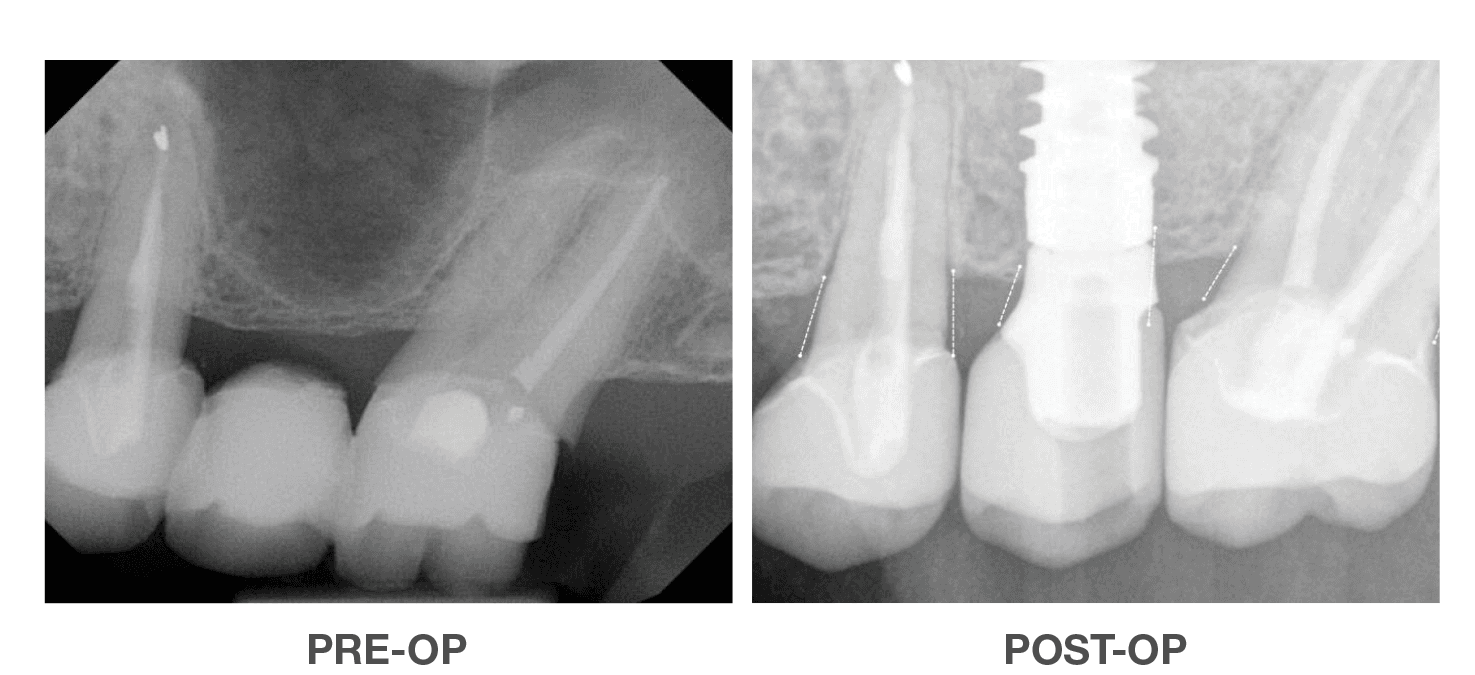

Successful Vertical & Horizontal

Augmentation to Repair Failed Implant

Using OraGen® Cellular Bone Matrix

Case performed by: Dr. Robert Miller, Plantation FL